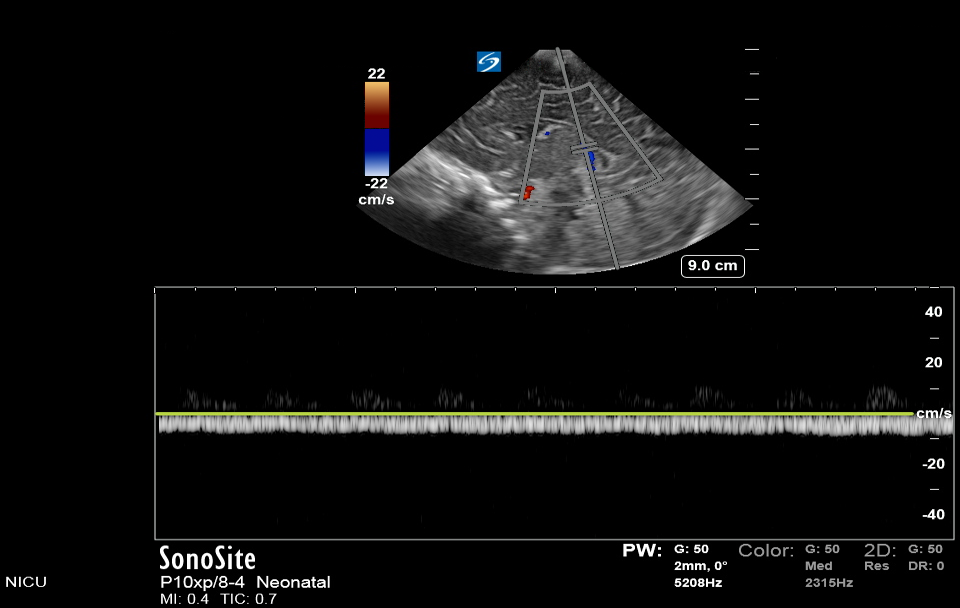

Neonatology Doppler Study of Internal Cerebral Vein Image